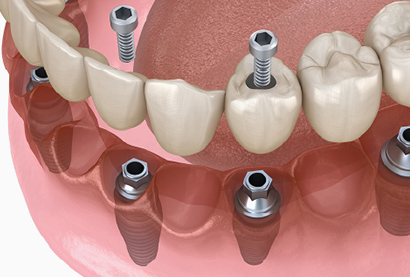

オペの手順

1切開

局所麻酔をかけて歯肉を切開し、顎の骨を露出させます。

2骨への穴あけ(ドリリング)

麻酔がしっかり効いているため、痛みはありません。細いドリルから順に太いドリルへと段階的に穴を拡げ、インプラントを埋め込むスペースを作ります。

3インプラント埋入

人工歯根となるインプラント体を作成した穴にしっかりと埋め込みます。切開した歯肉を縫合し、インプラントと骨が結合するまで通常3~6ヶ月の治癒期間を設けます。この期間中はインプラントが安定し、しっかりと骨に固定されるのを待ちます。

4アバットメント装着と被せ物のセット

治癒期間が終わったら、インプラントに土台となるアバットメントを装着し、その上に人工の歯(被せ物)を取り付けます。これにより、自然な見た目としっかりとした噛み合わせが実現します。